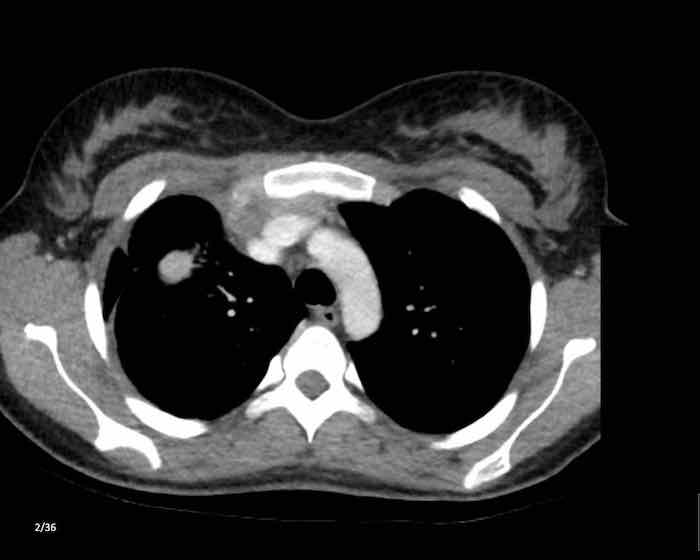

Các hình ảnh này của một nam giới 19 tuổi, được chụp CT để loại trừ thuyên tắc phổi.

Phát hiện tình cờ một khối ở khoang trước mạch máu.

Chẩn đoán có khả năng nhất là tăng sản tuyến ức và MRI được thực hiện để phân biệt thêm khối này.

Trên hình ảnh chuỗi xung T2W, tổn thương có tín hiệu tăng nhẹ.

Trên hình ảnh pha đối (out-of-phase), không có sự sụt giảm tín hiệu đáng kể.

SII nhỏ hơn 9%.

Do bệnh nhân không có bất kỳ triệu chứng nào, đặc biệt không có các triệu chứng có thể liên quan đến u lympho, và vì u tuyến ức (thymoma) là một khối u hiếm gặp, quyết định được đưa ra là theo dõi sau sáu tháng.

Tại thời điểm theo dõi sáu tháng, tuyến ức có hình ảnh bình thường.

Kết luận được đưa ra là đây là tăng sản tuyến ức hoặc mô tuyến ức tồn dư kích thước lớn, đã thoái triển trong vòng sáu tháng.